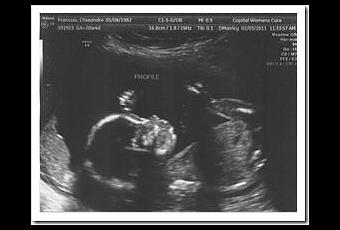

Pendant qu’elle prenait les mesures de notre bébé, nous nous régalions des images sur le grand écran. On a bien vu ses pieds et ses mains avec 5 orteils pour chaque, son profil et son nez en trompette. Le cœur et les autres organes sont tout bien comme il faut. Son poids est estimé à 400 grammes et sa taille (tête-fesse) à 14cm.

A la fin, elle nous demande si on veut savoir ce que c’est … oh que oui !! On avait eu beau bien regarder … on avait rien vu. Donc elle se positionne entre les jambes de l’arsouille et on voit apparaitre sur l’écran :

♀It’s a girl !♀